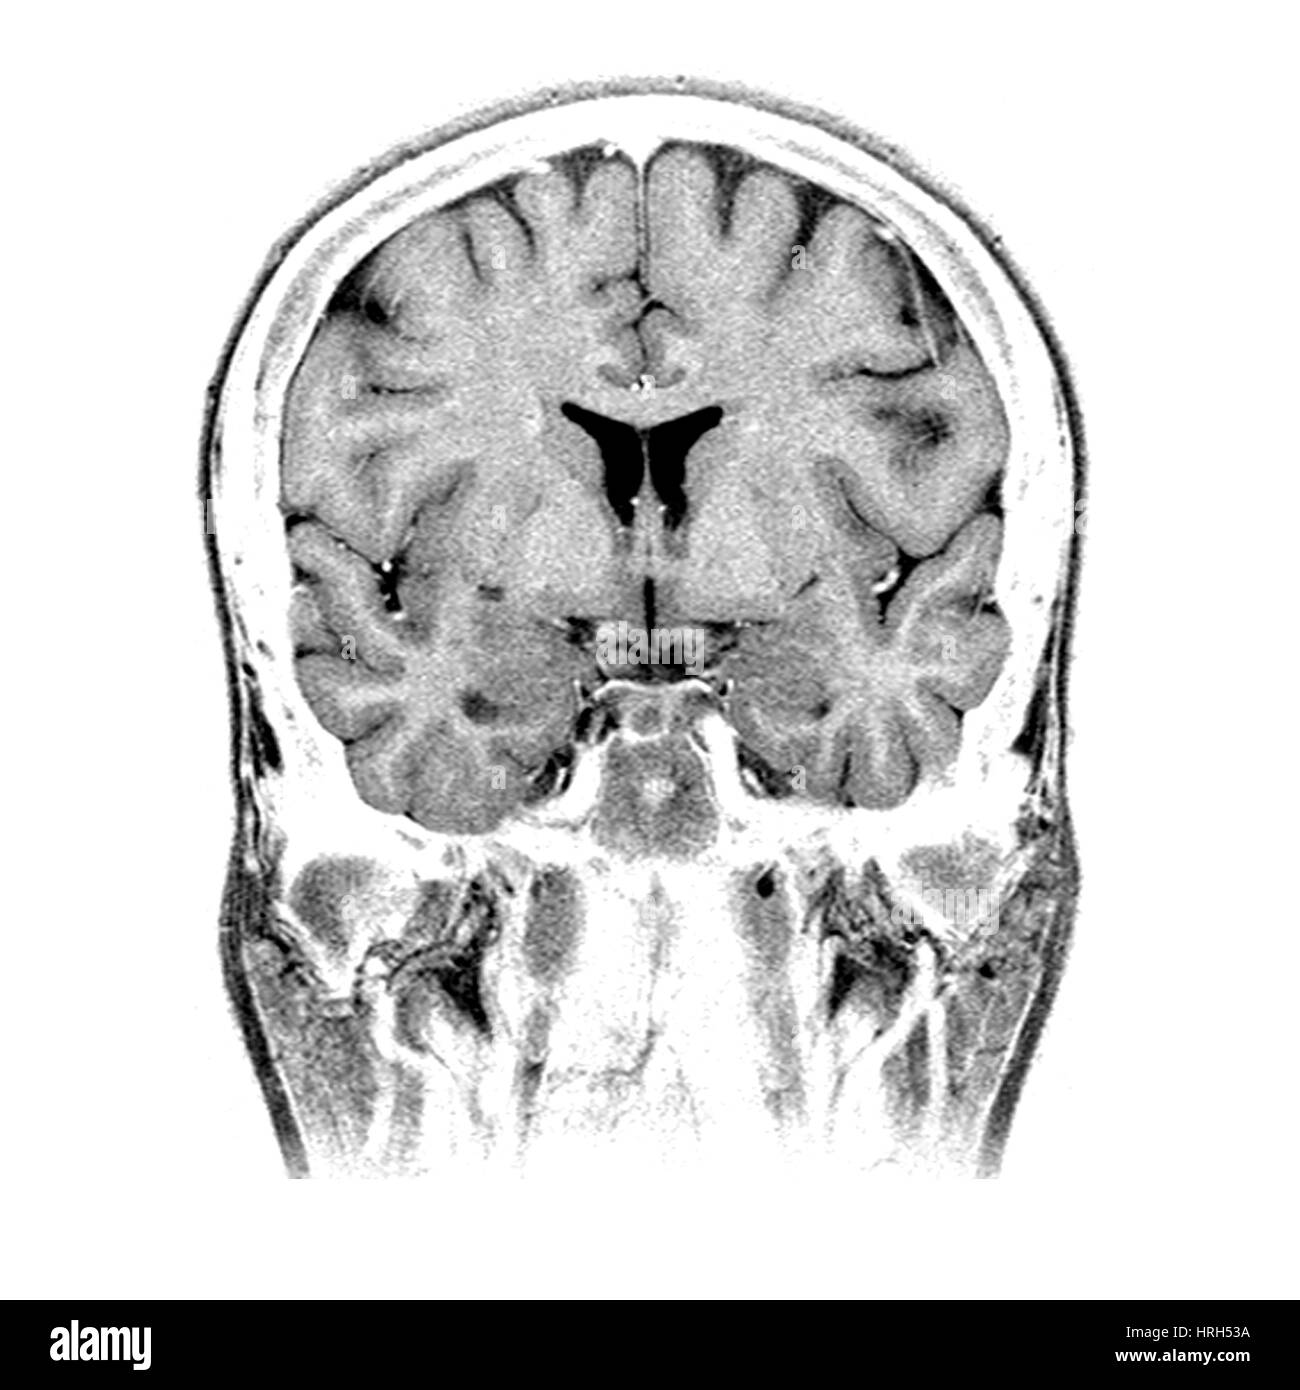

Lista muestra hermosas imágenes de resonancia magnética cerebral normal y anormal dinosenglish.edu.vn para que puedas explorar más en detalle.

resonancia magnética cerebral normal y anormal Pin en NEUROCIENCIAS resonancia magnética de cerebro Resonancia magnética (RM) de cerebro, corte axial ponderado en T2: la … VIDEO Nueva mancha en la Resonancia

Engineer Team : RESONANCIA MAGNETICA Magnetic Resonance Imaging – Clinical Images Hallazgos por resonancia magnética cerebral de nuestro paciente. M, 21 … Imágenes por resonancia magnética anormales como predictoras de mal … Imágenes por resonancia magnética anormales como predictoras de mal … Lesiones en resonancia magnética (RM) del encéfalo y la médula espinal … Pin en Resonancia Magnética del Encéfalo A) Resonancia magnética cerebral (RMC) mostrando infartos en … Caso 1: Edema cerebral visualizado mediante RM. (A) Secuencia T1 plano … Rascacielos dormir pasta tac y resonancia diferencias retrasar … Pin on Apuntes de Enfermería y T.C.A.E Resonancia magnética cerebral secuencia T2, que muestra lesión … Meningitis aguda en la enfermedad de Behçet | Reumatología Clínica Resonancia magnética coronal normal del cerebro Fotografía de stock – Alamy Imágenes de resonancia magnética, la imagen de la cabeza en diferentes … Resonancia magnética cerebral A) protocolo T1 sagital (Caso 1). Se … Resonancia magnética cerebral. Secuencia T1 corte sagital. Atrofia … Resonancia magnética de cerebro, cortes axiales, secuencias T2. Señal … Resonancia magnética de cráneo. A y B) Cortes axiales FLAIR … Resonancia magnética (RM) de cerebro, corte axial ponderado en T2: la … RM cerebral: Interpretación paso a paso | Kenhub Resonancia magnética de cerebro, cortes axiales, secuencias T2. Señal … De Resonancia Magnética De Cerebro Foto de archivo – Imagen de arteria … Top 107+ Imagenes de resonancia cerebral normal – Destinomexico.mx -Imagen por resonancia magnética del cerebro. a) Cortes sagital y axial … resonanCia magnétiCa Cerebral donde se observa hiperintensidad a nivel … MRI (Imagen de resonancia magnética) – Tomografía computarizada de la … Meningioma – NCI Imágenes por resonancia magnética coloreadas del cerebro sano del … Resonancia magnética cerebral en secuencia FLAIR, que muestra lesiones … Contraste resonancia magnetica cerebral – senturinthegreen Relación de los espacios de Virchow-Robin con la enfermedad de … Gliomatosis cerebral – Instituto Nacional del Cáncer Pin en Neurology. Recomendaciones para la utilización e interpretación de los estudios de … Fotografía De La Proyección De Imagen De Resonancia Magnética Del … atmósfera Dirigir Cumplir anatomia resonancia magnetica Desarrollar … Pin en #MEDICINA,#SALUD Resonancia magnética de la nasofaringe De Resonancia Magnética De Cerebro Foto de archivo – Imagen de polilla … Atrofia cortical global de predominio parietal en la Resonancia … Resonancia magnética cerebral | Download Scientific Diagram Neuroblog: Resonancia magnética cerebral en la trombosis crónica de … De Resonancia Magnética De Cerebro Imagen de archivo – Imagen de … ¿Cuáles son los riesgos de la resonancia magnética? – Integra Salud … Resonancia magnética cerebral al decimocuarto día de ingreso: área … Resonancia magnética. Corte axial mostrando área infartada en el … Resonancia magnética cerebral del paciente AV evidenciando lesiones en … -Ressonância magnética de encéfalo mostrando múltiplas imagens … Resonancia magnética cerebral secuencia FLAIR (Fluid Attenuated … Resonancia magnética cerebral con protocolo de epilepsia, en sección … Resonancia magnética cerebral en corte sagital. Se observa una evidente … Resonancia magnética craneal en la que se evidencian lesiones … Logran visualizar el cerebro a detalle más completo tras una resonancia … Así decide el cerebro la severidad de un castigo De Resonancia Magnética De Cerebro, Imagen de archivo – Imagen de … A) Resonancia magnética cerebral; Secuencia Tof: oclusión de arteria … Un estudio asocia la ansiedad con la aparición rápida del Alzheimer IMÁGENES DE 18 F-PR04.MZ PET FUSIONADA CON RESONANCIA MAGNÉTICA … Imágenes por resonancia magnética anormales como predictoras de mal … Tumores de la región pineal – Instituto Nacional del Cáncer Epilepsia: una historia de voces y fantasmas | Neurología Contribución de las imágenes de resonancia magnética por tensor de … Resonancia magnética secuencia T2 plano coronal de quiste epidermoide … Resonancia Magnética Cerebral del paciente: a. Aumento de… | Download … Resonancia magnética cerebral 2022 Síndrome de hemiconvulsión-hemiplejía-epilepsia. Seguimiento de un caso … Enfoque Radiologico: La resonancia magnética permite detectar lesiones … Resonancia magnética craneal T1 con contraste que muestra angiomatosis … guidewiz – Blog Resonancia magnética cerebral, secuencia SWI. Ribete hipointenso en la … resonAnCiA mAgnétiCA de ColumnA Con gAdolinio. Corte sAgitAl en t1 de … SEMANA 12: FUNDAMENTOS DE RESONANCIA MAGNÉTICA NUCLEAR. INDICACIONES Y … DIAGNÓSTICO DE ESCLEROSIS MÚLTIP Magnetic resonance imaging of the brain – Alchetron, the free social … Resonancia magnética de órbitas | Instituto Radiológico Dr. E Castillo Alteración de la marcha en un paciente post-trasplante hepático Resonancia magnética cerebral de un paciente sano (Ay B) y paciente que … Utilidad de la resonancia magnética craneal para el diagnóstico de la … Resonancia Magnética Del Cerebro El Tumor Cerebral Foto de stock y más … De Resonancia Magnética De Cerebro Imagen de archivo – Imagen de … ABDALLA RADIOLOGIA: NEURINOMA ACUSTICO Atrofia cortical global de predominio parietal en la Resonancia … Resonancia Magnética : Producción de la imagen MRI Brain Scan — Stock Photo © Bunyos30 #18724051 Mri (imagen de resonancia magnética) Monitor con imagen de captura de … Tomografía computarizada vs resonancia magnética: diferencia y … Tumores Cerebrales – Unidad de Neurocirugía RGS Resonancia magnética de la columna, sección sagital. Observe los discos … La resonancia magnética, una técnica imprescindible en el diagnóstico … Perfusión Cerebral por Resonancia Magnética | ¿Qué es? ¿Necesita Contraste? Resonancia Magnética Cerebro A: resonancia magnética, T2 coronal preoperatoria; se observa lesión en … Resonancia magnética cerebral — Foto de stock © Bunyos30 #27340623 La resonancia magnética se perfila como detector de mentiras | Futuro … Resonancia magnética cerebral en T1 con gadolinio, cortes axial (a … MRI brain : show brain tumor at right parietal lobe of cerebrum — Stock … NEUROIMÁGENES EN ENFERMEDAD DE PARKINSON: ROL DE LA RESONANCIA …